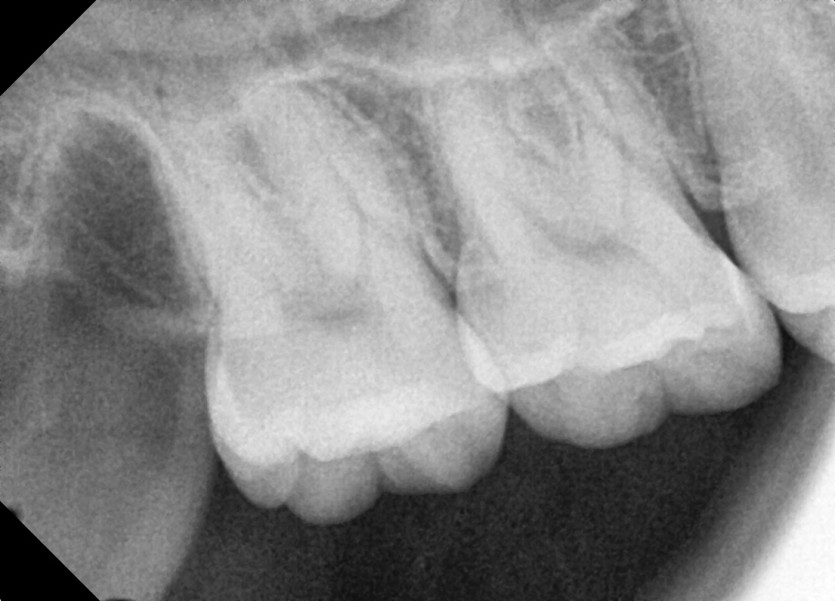

#18,48 사랑니 발치

구강외과 전문의가 당일 발치했습니다.